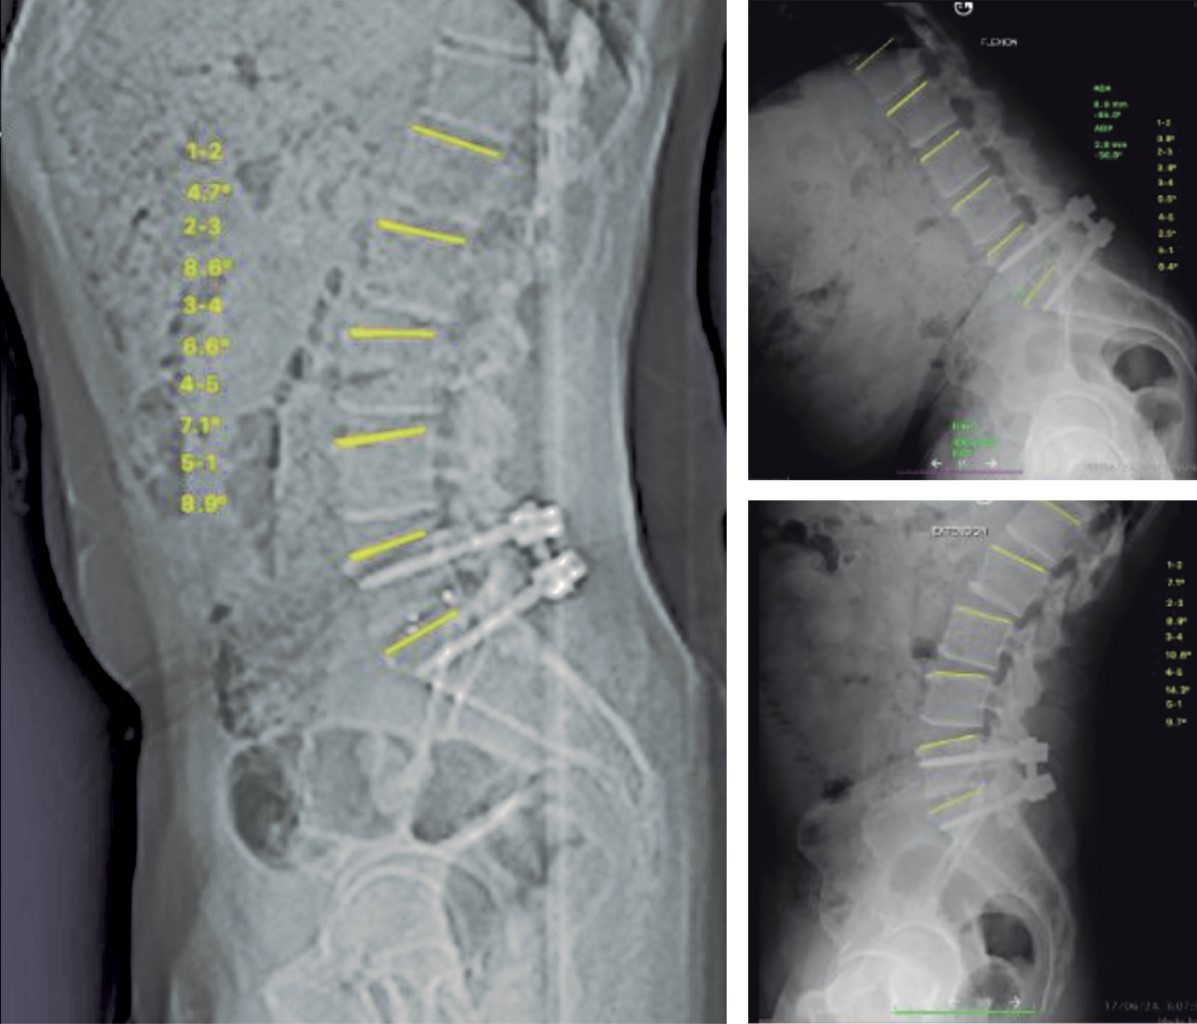

Masculino de 65 años, con dolor lumbar refractario y claudicación posterior a la fusión intervertebral lumbar transforaminal (TLIF, por sus siglas en inglés) L5-S1, hace cuatro años. Se evidencia enfermedad de segmento adyacente, listesis L4-L5 grado 1, pseudoartrosis L5-S1 y fractura del tornillo de S1 izquierdo. Con incidencia pélvica 44.2, inclinación pélvica 5.6, pendiente sacra 38.7, lordosis lumbar 57, lordosis segmentaria 45.4 (Roussouly tipo 3 antevertido) (Figura 1).

Figura 1